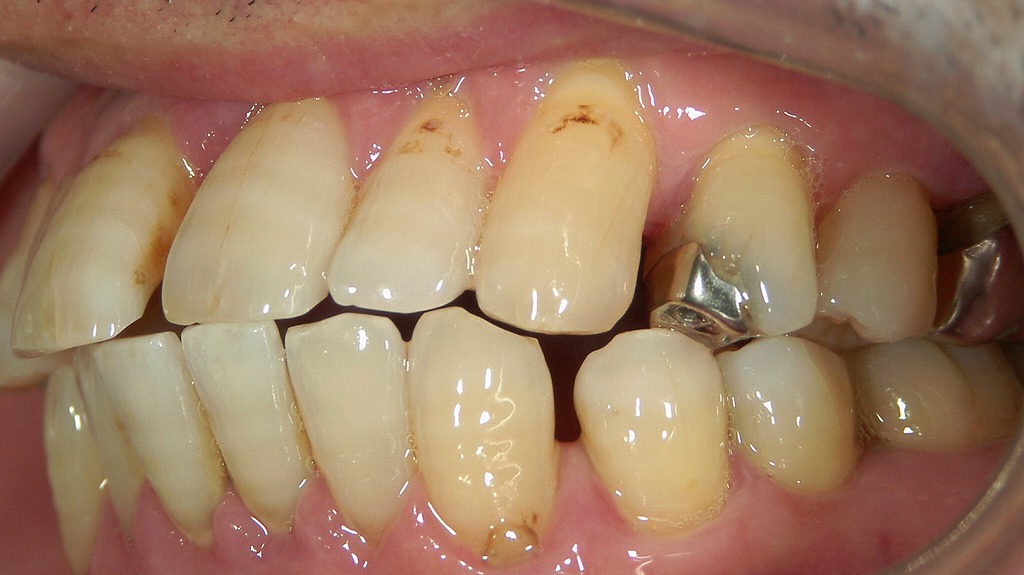

画像でも見られるように、

前歯部に多数の隙間が見えるのは 歯周病による典型的変化 です。

③ 歯の向きが変わる → 特に前歯が前に倒れ出っ歯になる

歯槽骨が減ると、歯は支えを失い本来の位置をキープできなくなります。

● 前歯は“前方へ倒れる(フレアアウト)”傾向が強い

- 結果として、歯冠が前に傾斜 → 出っ歯のような見た目に

→ 歯周病が「後天的な出っ歯」を作り出すことは珍しくありません。

● 下の前歯は内側に倒れ込む場合も

噛み合わせの力の影響で、

上が前へ、下が内側へとズレるため、

咬合が崩壊し、さらに歯の隙間が広がりやすくなります。

歯周病の進行によって起こるフレアアウト(前歯の倒れ込み)症例

下顎前歯の舌側に大量の歯石が付着し、歯周病が進行している状態です。

歯を支える骨や歯周組織が弱くなると、前歯は内側からの舌の圧や噛み合わせの力に耐えられず、徐々に前方へ倒れ込む「フレアアウト」を起こします。